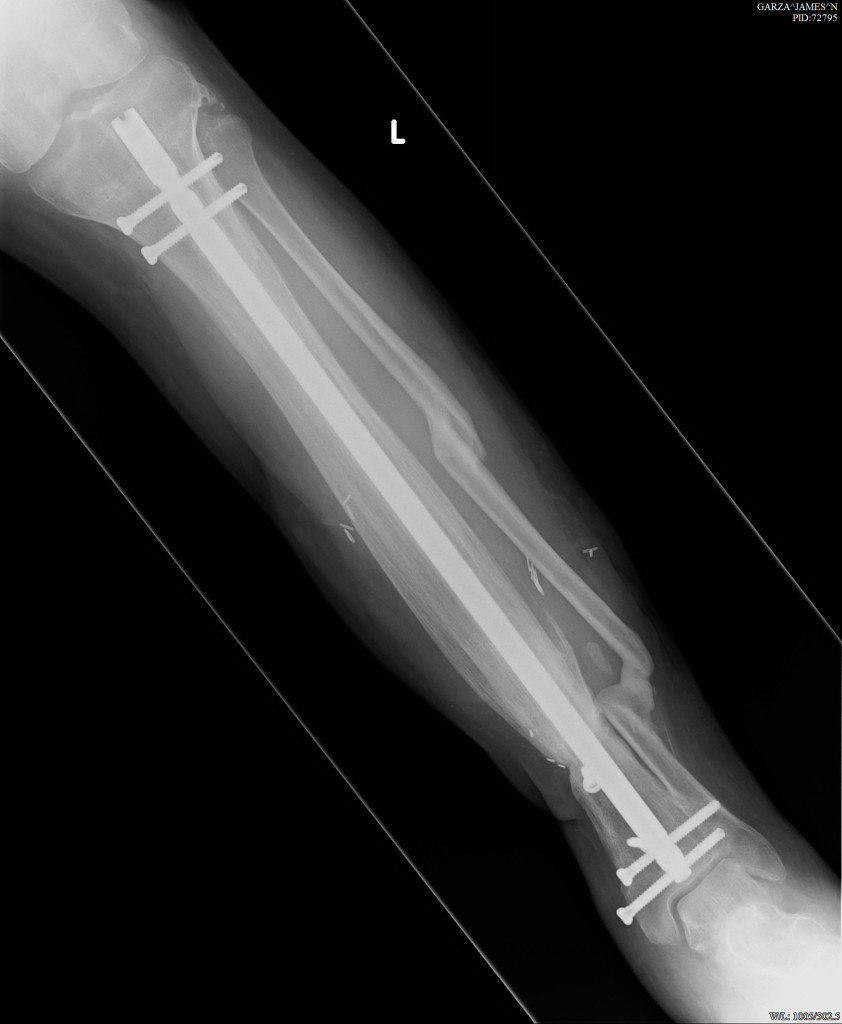

I had polio as a child. After many surgeries over a 30 year period my walking was getting increasingly more difficult. Walking hunched over and holding on to my right leg not to have it collapse underneath me. I started visiting doctors in Western NY and Canada only to be told that either nothing could be done or something might be possible but they could not help me. Finally a doctor suggested HSS. Calling the hospital I was directed to Dr. S. Robert Rozbruch. We met and he told me he could help, an open wedge osteotomy with a correction of the varus. Surgery was a life changing experience. Instead of being relegated to a life of walking with assistance or worse, I now walk with ease completing tasks which were once seemed daunting. I never gave up looking for help and I never thought i would have found someone as amazing as Dr. Rozbruch.